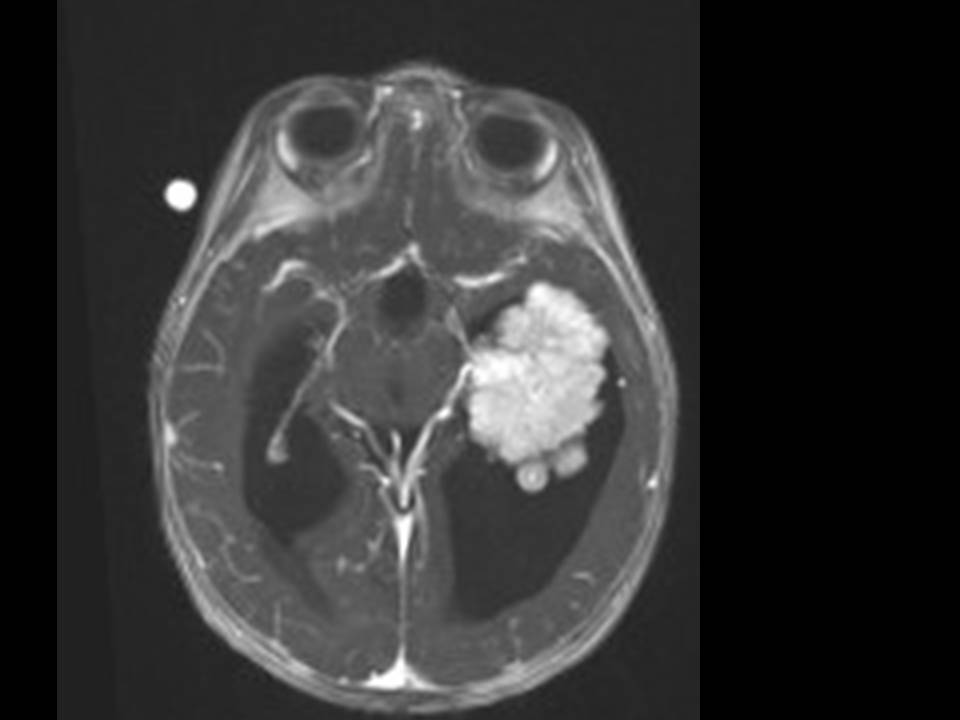

10 Monate altes Mädchen. Der Kinderarzt stellt fest, dass das kleine Mädchen einen recht großen Kopfumfang hat, nicht mit den Augen fixiert und anscheinend auch nicht richtig sehen kann. Damit bestätigt er die größten Befürchtungen der Eltern, denen in den letzten Wochen aufgefallen war, dass ihre Tochter nach keinem Spielzeug mehr greift und sie nur dann anlächelt, wenn sie zu ihr sprechen.

Bildgebung - MRT